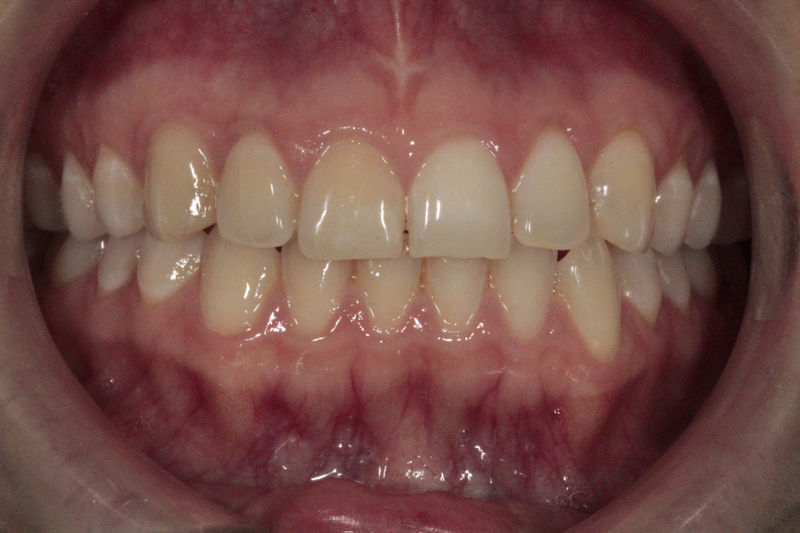

Cirugía ortognática, implantes, carillas y coronas,